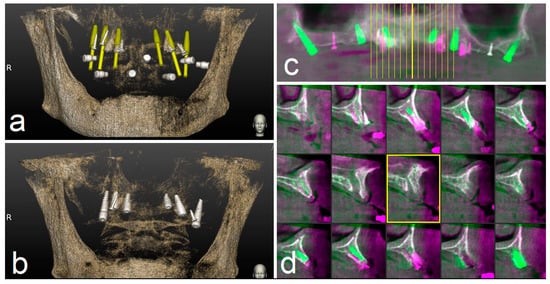

The preoperative surgical plan and the postoperative CBCT were superimposed using an accuracy evaluation software (EvaluNav™) part of Navident™ navigation system (Claronav Inc., Toronto, YTO, Canada). Calibration was done directly between the two volumetric images (Figure 8). Software provides various visualization tools that confirm two CBCTs are precisely matched. Once the user is satisfied with volumetric registration, the software automatically matches the planned implant shape onto the post-operative image and computes deviations between the planned and placed implant locations (Figure 9).

Figure 8.

The preoperative surgical plan (a) and the postoperative cone beam computerized tomography (CBCT) (b) were superimposed using accuracy evaluation software (c,d). The registration was performed directly between the two volumetric images.